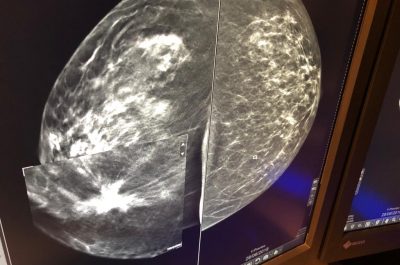

Mammografia 3 D, scoprire i tumori “invisibili”: ecco come funziona e quando è necessaria la tomosintesi